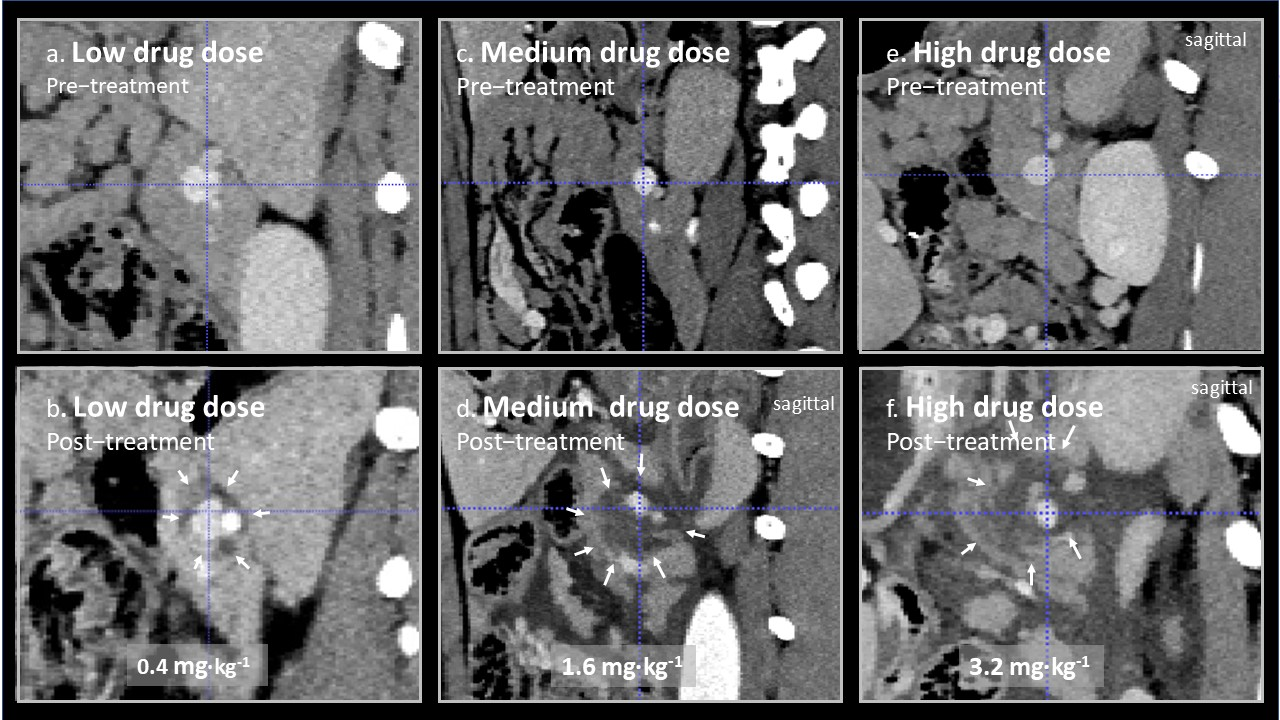

In Figure 2, representative images from treated splenic veins are shown in the plane perpendicular to the axis of the treated vein, below an image of the same area prior to treatment for animal 3 (low drug dose), 5 (medium drug dose), and 7 (high drug dose). Perivascular oedema was observed at all doses. In animal 3, it is doubtful weather there was any effect beyond oedema, but circumferential perivascular necrotic margins of increasing size were seen as the drug dose was increased.

Figure 2.

(a–f) Contrast-enhanced CT scans of treated splenic veins (blue dotted cross-hair) were taken before and 2 days after EPA. Areas of reduced uptake of contrast after treatment are marked by small arrows. The changes in animal 3 treated at a low Verteporfin dose of 0.4 mg∙kg−1 (a,b) are small, possibly perivascular oedema, and of questionable significance, but are of increasing size when the Verteporfin dose was increased to 1.6 mg∙kg−1 animal 5 (c,d) and 3.2 mg∙kg−1 (e,f), in animal 7. Lesions seen on CT were confirmed on histology to be due to pancreatic necrosis. The light dose was nearly constant for these three animals at 377, 311, and 321 J∙cm−1, for animals 3, 5, and 7, respectively (Table 1).